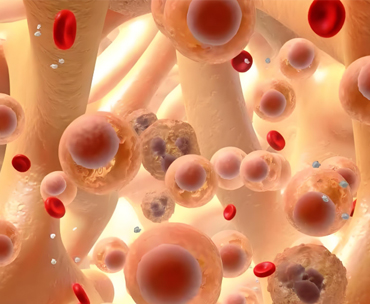

肾癌是肾脏细胞发生癌变形成的恶性肿瘤,每 10 万人中约有 4-5 人患病,男女发病比例约为 2:1,男性患病率相对更高。在肾癌中,绝大多数源于肾小管上皮细胞,即肾细胞癌。

• 遗传因素也不容忽视,例如常染色体显性遗传的冯・希佩尔 - 林道病(VHL 病),患者易患肾癌中的透明细胞癌。此外,不同组织学类型的肾癌存在不同的染色体异常,治疗效果也因此有所差异。